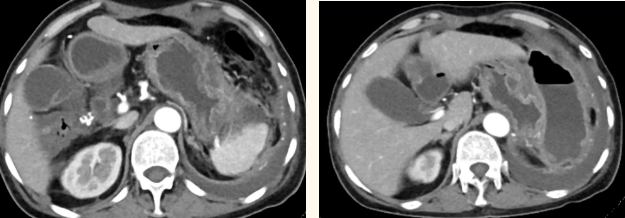

一籌莫展的她終于在病友的介紹下,來(lái)到西安國(guó)際醫(yī)學(xué)中心醫(yī)院找到蔡磊主任。經(jīng)過(guò)詢問(wèn)病史,查體等,蔡磊主任建議口服索坦治療。3個(gè)月后,李阿姨復(fù)查CT提示胃間質(zhì)瘤較前明顯縮小,大小約10.4cm?6cm。但仍存在消化道出血,營(yíng)養(yǎng)狀況差,全身無(wú)力,骨髓抑制。蔡磊主任隨即將患者收治入院。